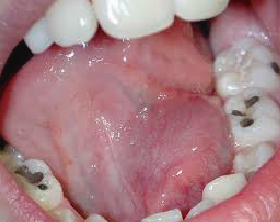

También llamada Medicina Bucal, es la rama de la odontología que se encarga del diagnóstico y manejo de las enfermedades propias de la boca y de las enfermedades sistémicas (de otros sitios del organismo), que tienen manifestaciones bucales.

• El cáncer oral, el diagnóstico y tratamiento quirúrgico de la lesión y la rehabilitación con la somato prótesis. También se encarga del manejo de las implicaciones o consecuencias de la radioterapia y quimioterapia.

El estomatólogo hace parte de un equipo de salud y está en la capacidad de diagnosticar patologías infecciosas, tumorales y de malformación, tomar biopsias y realizar tratamientos de urgencias, de síndromes dolorosos y disfunciones miofaciales y de la articulación temporo mandibular (ATM).